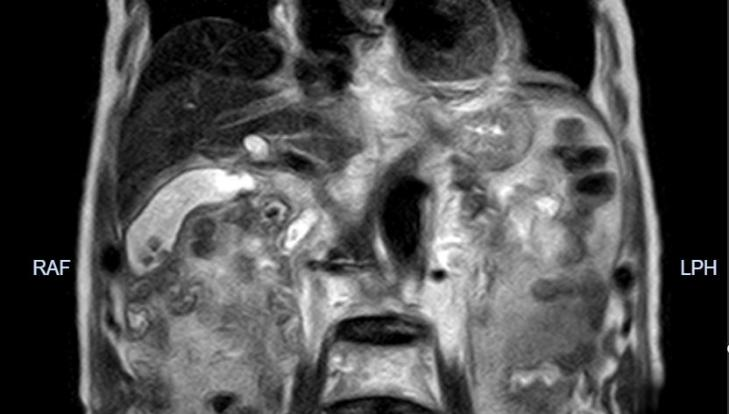

患者磁共振成像

郝琪伟主任迅速组织高庆东副主任医师、王林主治医师等团队成员,对谢大爷的病情进行细致全面的检查评估。经综合考量患者身体状况,并与患者家属充分沟通后,决定为其实施免T 管的腹腔镜胆囊切除+胆道探查取石+一期缝合术(LCBDE)。在麻醉手术科王文文麻醉师的支持下,手术团队凭借丰富的经验和娴熟的技术,从麻醉、布孔到手术结束仅耗时1个多小时,顺利实施腹腔镜胆囊切除+胆道探查取石+一期缝合术。术后,患者麻醉苏醒顺利,恢复良好,术后第一天即可进食流食。患者家属激动地说:“这么小的伤口就解决了老爷子的大毛病,你们不仅技术精湛,更是给了我们全家安心和希望,真的太感谢了!”